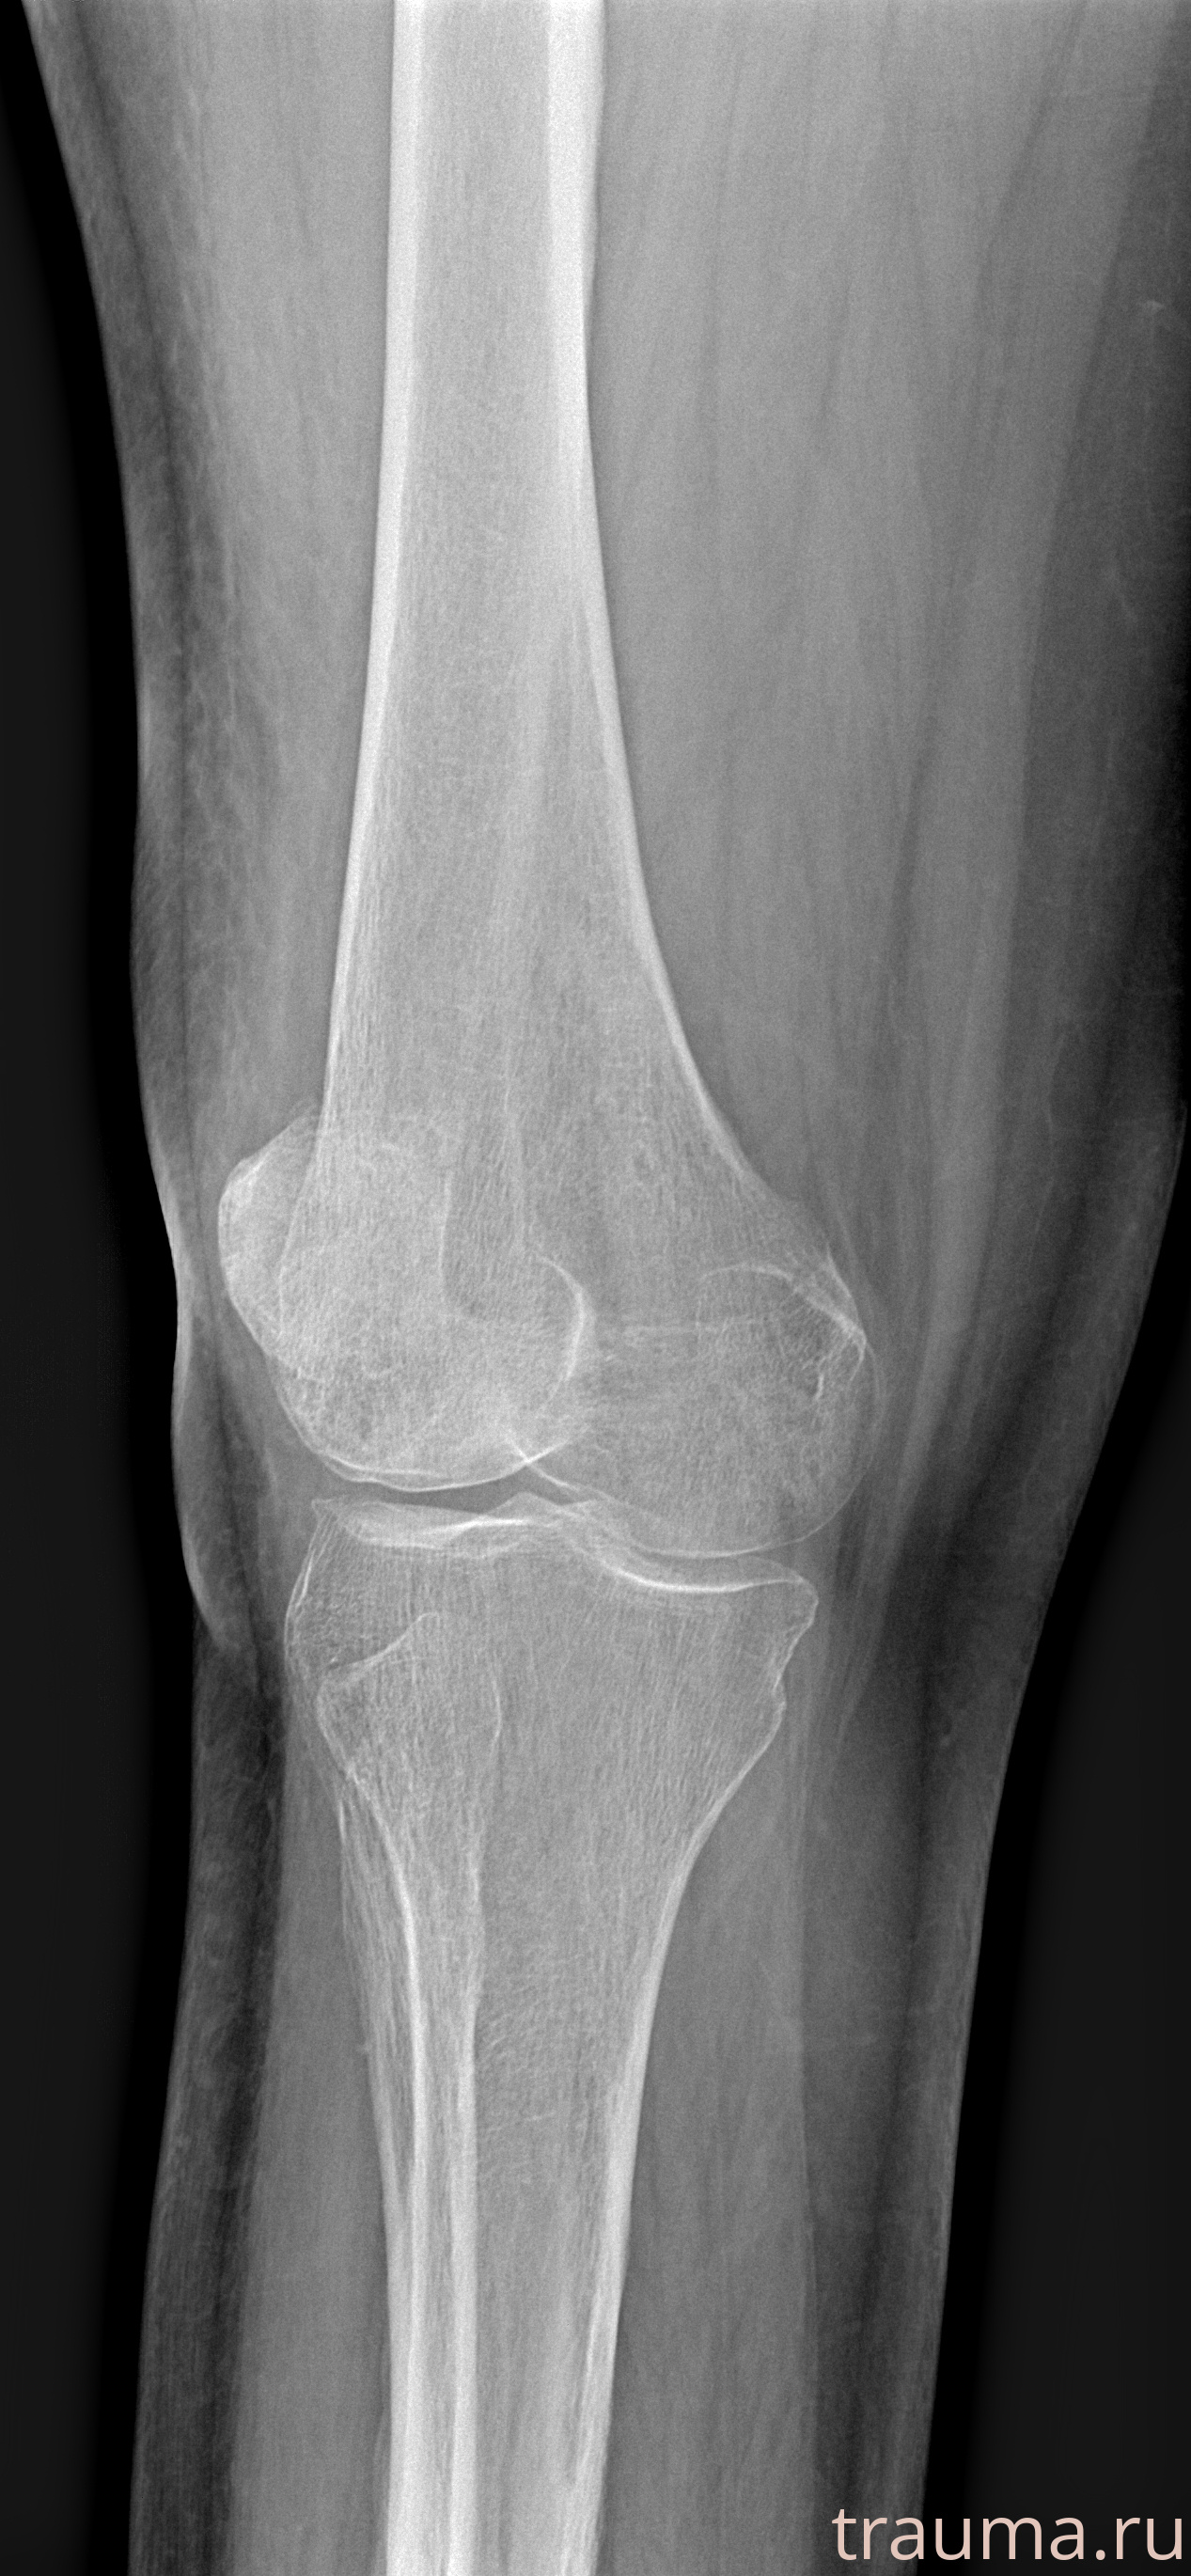

Рентгенограммы

Рентген на дому: по вашему адресу приезжает врач-рентгенолог, травматолог-ортопед с мобильным рентгеновским аппаратом, проводит диагностику травмы или заболевания, делает необходимые рентгенограммы, дает рекомендации по дальнейшему лечению. Получить качественные снимки в домашних условиях возможно благодаря уникальной методике, разработанной МосРентген Центром для института  Склифосовского